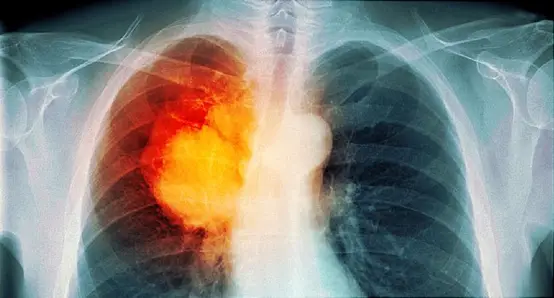

肺空洞,这是一个令人心生恐惧的词汇。作为一名饱受肺空洞困扰的患者,我深知其中的痛苦和折磨。今天,我将以一个亲身体验者的角度,向大家揭示肺空洞形成的奥秘。

在我年轻时,我曾经是一个烟民。每天都会吸上几包烟,仿佛这是我的生活必需品。然而,我从未意识到抽烟对肺部的危害有多么巨大。长时间吸入有害物质会导致肺组织受损,并最终形成肺空洞。就像我一样,许多人都因为不慎陷入了这个无底深渊。

在我得知自己患上肺结核后,感到十分恐慌。然而,在接受治疗期间,我并没有完全按医嘱去执行。我没有坚持完整的治疗疗程,而是过早地停药。这个错误的决定给了肺空洞一个机会。肺结核是肺空洞的重要诱因之一,如果不加以重视和及时治疗,后果将不堪设想。